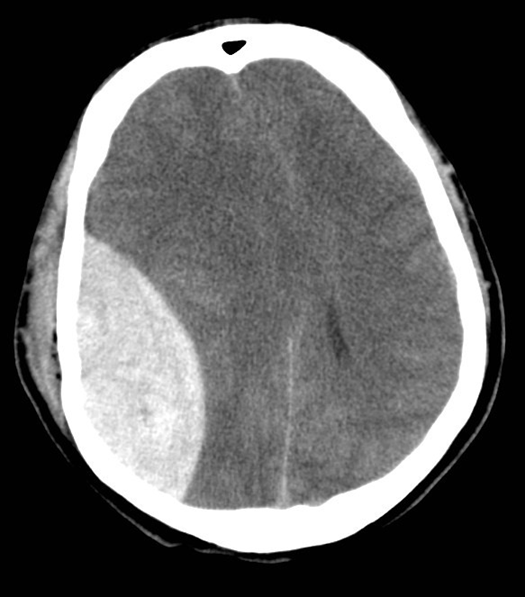

How are Intraparenchymal Hemorrhages imaged?

Intraparenchymal hemorrhages are best imaged using a CT scan

→ in an acute setting, blood will appear white bright in the brain

→ MRI or vascular studies may be used in order to find the underlying vascular lesions